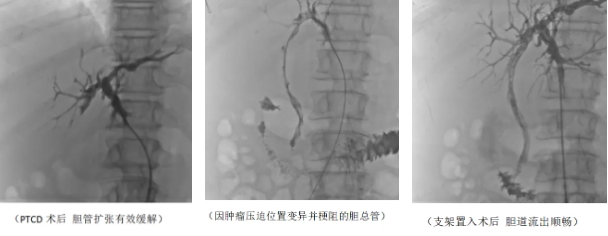

经过两周精心调养,患者的身体状况达到二期手术标准。第二期手术的关键——胆道支架置入术正式开展。专家团队再次凭借丰富经验和高超技术,将支架精准放置在被肿瘤压迫位置变异的胆总管狭窄部位。这个金属支架如同坚固的桥梁,稳稳支撑起狭窄的胆管,重建胆汁流出道。术后复查显示,支架位置良好,胆汁引流通畅无阻,李先生的胆红素水平基本恢复正常,困扰他许久的黄疸症状彻底消失,生活质量得到极大改善。

胆道支架置入术是将金属或塑料支架植入胆道狭窄部位,恢复胆汁正常流通的治疗方法。它就像在胆道的 “交通拥堵路段” 修建了高架桥,让胆汁能够顺利通行。该手术适用于恶性肿瘤压迫、侵犯胆管,以及胆管良性狭窄等病症。支架置入后,胆汁可通过支架直接流入肠道,实现生理性引流,相比外引流,能减少胆汁丢失,维持机体消化功能,显著提升患者生活质量,延长生存期。